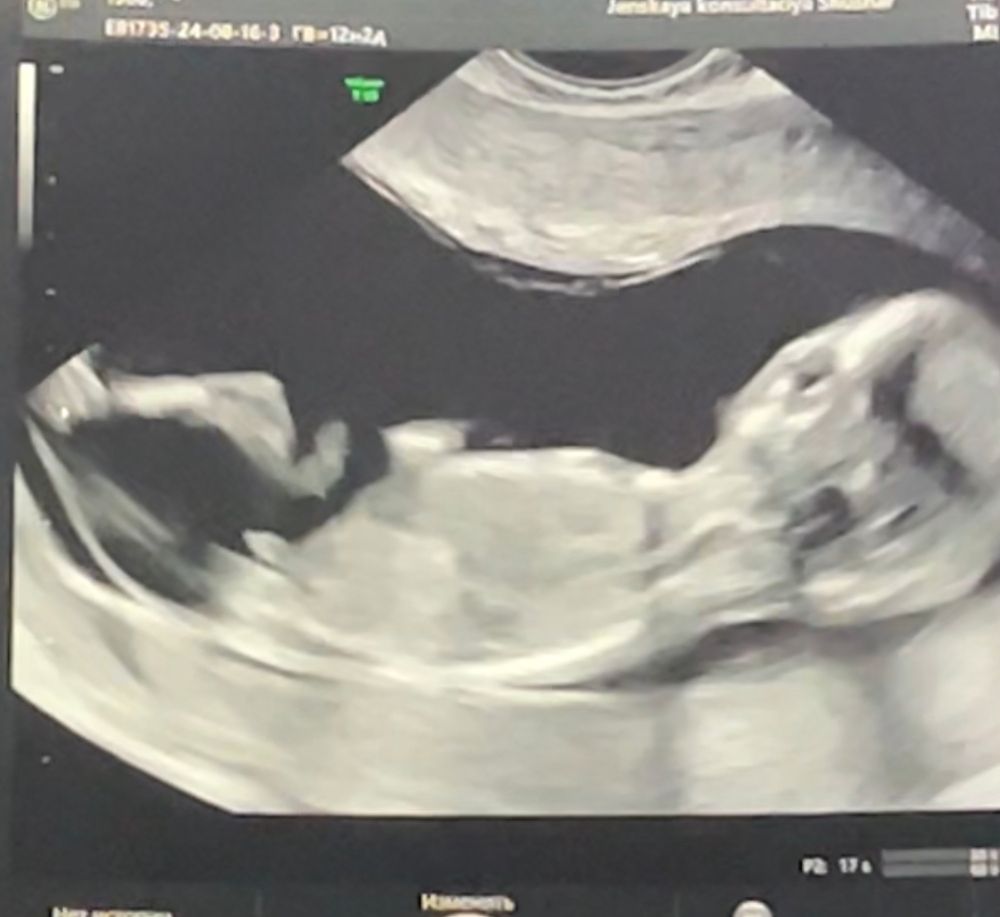

Мальчик или девочка?

Тест по крови определил Изображение мальчика

Мне мальчик виднеется, угол вроде как раз острый

Анастасия , на узи тоже Предположили мальчика